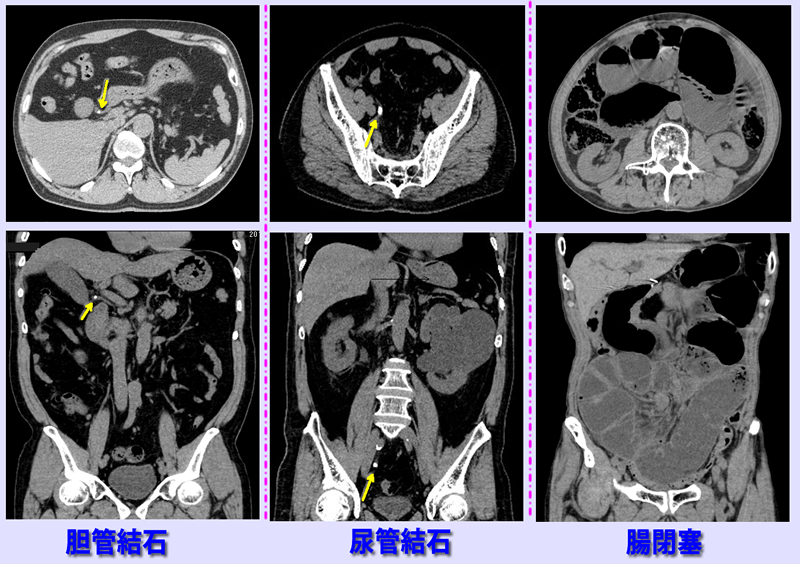

上腹部痛が持続するため夜間11時来院。左CT画像で胆管内に結石(黄色矢印)認め、胆管結石、胆管炎と診断。

中央CT画像は腹部から背部の痛み,吐き気で受診。右尿管結石(黄色矢印)と判明。

右CT画像は腹痛と嘔気で受診。腸内に多量の空気、内容物貯留認め腸閉塞と判明